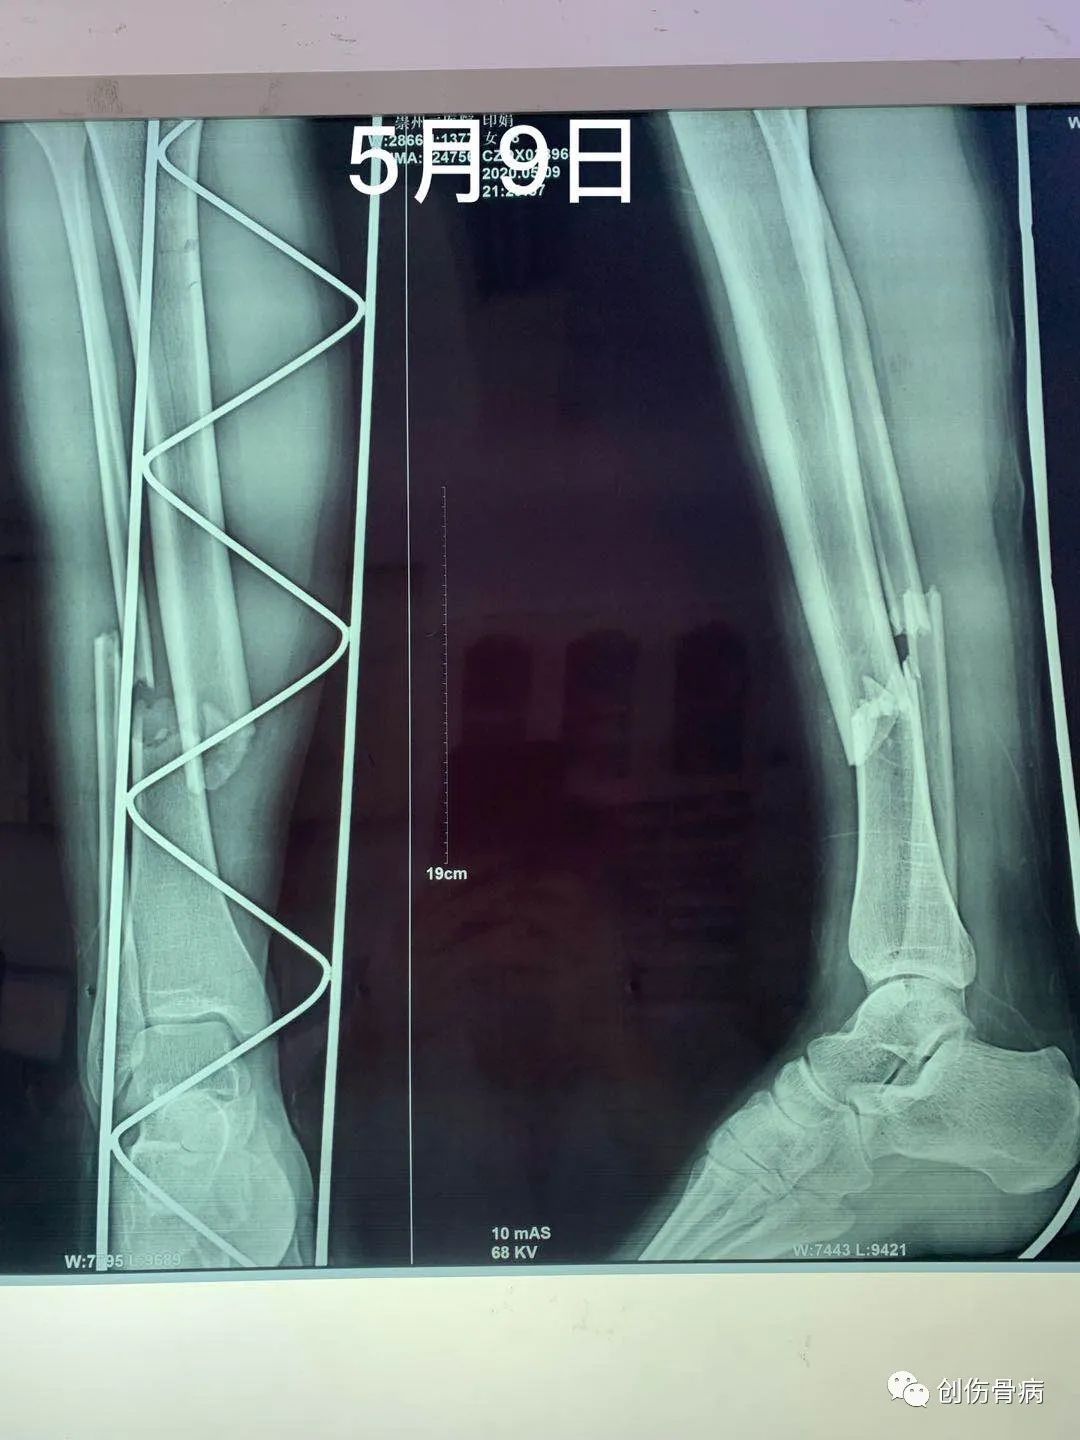

都说车祸无情,但是创伤后的并发症也依旧无情。2020年5月9日21时55分我科室接收一名18岁外伤小妹妹,当天晚上小妹妹跟爸爸妈妈路边散步被一汽车撞倒受伤,送至我院时就是一单纯右胫腓骨下段粉碎性骨折伴头皮裂伤,入院行右小腿DR及胸部CT示:2020年5月12日14时左右,小妹妹突然出现呼吸困难、烦躁不安,氧饱和度40-50%,家属诉小女孩昨日夜间有偷偷咳嗽的表现,当班医生一看就考虑脂肪栓塞立即给与安排行胸部CT示:

肺部情况稳定后于2020年5月28日行右胫腓骨下段粉碎性骨折手术治疗